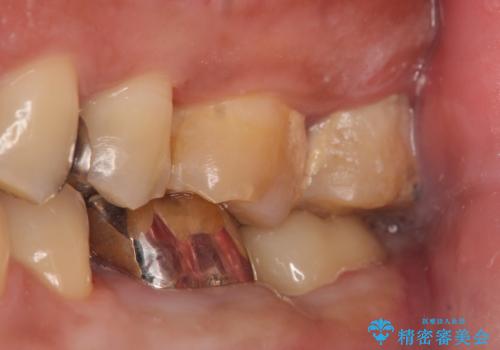

- 左下7の歯しみる、被せ物を被せてもすぐに外れてしまうといらっしゃった方の症例です。

左下に被せ物を被せるクリアランス(補綴のための上下のスペース)ないため、十分な歯冠長を確保するため歯冠長延長術を行いました。

その後歯肉の回復を待ち、フルジルコニアクラウンにて補綴を行いました。